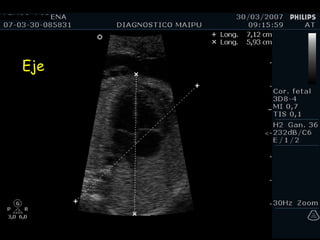

Eje

Tamaño